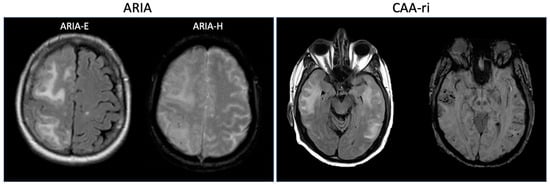

- Antolini, L.; DiFrancesco, J.C.; Zedde, M.; Basso, G.; Arighi, A.; Shima, A.; Cagnin, A.; Caulo, M.; Carare, R.O.; Charidimou, A.; et al. Spontaneous ARIA-like Events in Cerebral Amyloid Angiopathy-Related Inflammation: A Multicenter Prospective Longitudinal Cohort Study. Neurology 2021, 97, e1809–e1822. [Google Scholar] [CrossRef]

- Ryan, N.S.; Lashley, T.; Revesz, T.; Dantu, K.; Fox, N.C.; Morris, H.R. Spontaneous ARIA (Amyloid-Related Imaging Abnormalities) and Cerebral Amyloid Angiopathy Related Inflammation in Presenilin 1-Associated Familial Alzheimer’s Disease. J. Alzheimer’s Dis. 2015, 44, 1069–1074. [Google Scholar] [CrossRef]